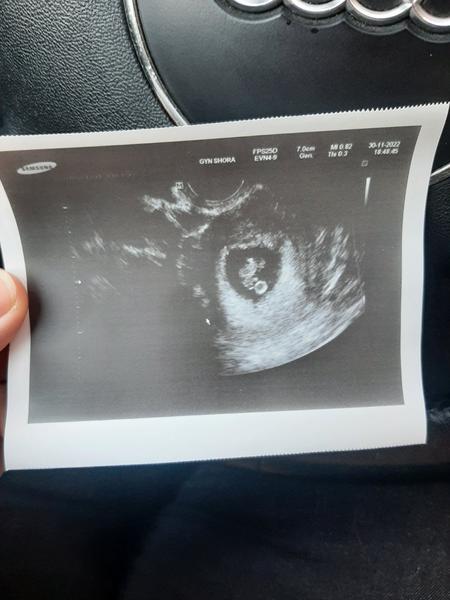

Ahoj holky, bohužel jsem musela na pohotovost, ale dobra zprava 6+3 a máme srdíčko❤️🙏🍀

Hlavně ze je vše v pořádku a skvělá zprava ohledně srdicka 🥰🥰

@kristynaprandl tak je všechno v pořádku. Srdicko bylo krásně vidět ❤ další kontrola 11.12. a ode dneška jsem doma 😊 napsal mi torecan na zvracení a mám odpočívat 😊